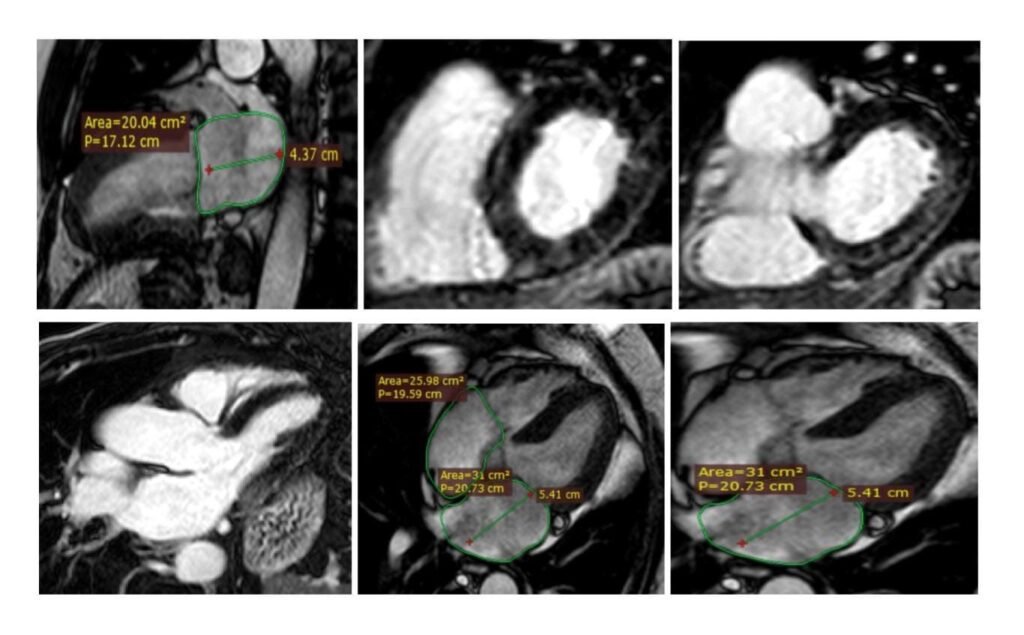

Recentemente, disponendo di adeguate risorse professionali e strumentali, gli ambulatori dell’ Emodinamica di Patti sono stati arricchiti di una nuova metodica ad altissima sensibilità e specificità diagnostica (diagnostica di III° livello), ovvero della Risonanza Magnetica Cardiaca eseguita in condizioni basali per lo studio di patologie cardiache tissutali, strutturali e valvolari, con l’obiettivo, entro la fine dell’anno, di estendere la sua applicazione alla ricerca della cardiopatia ischemica durante stress farmacologico (tecnica presente solo in pochi centri del Sud Italia). In un conteso di valida collaborazione tra l’Emodinamica di Patti e le Divisioni di Radiodiagnostica dei PP.OO di Milazzo e Barcellona PG, dirette dal dott. Simone Fogliani e dalla Dott.ssa Francesca Torre, la metodica in oggetto viene concretamente svolta da un team multidisciplinare di Cardiologi e Radiologi presso il Centro di Risonanza Magnetica Nucleare del PO di Barcellona PG, la cui apparecchiatura è dotata di modulo cardiaco Riguardo alla realizzazione di questa rilevante attività diagnostica multidisciplinare, a servizio del vasto territorio Tirrenico-Nebroideo, è doveroso esprimere gratitudine ai Vertici Aziendali dell’ASP Messina, in primo luogo al Direttore Generale dott. Giuseppe Cuccì, per l’imprescindibile supporto tecnico e la fiducia riposta. Un grazie per il contributo organizzativo va anche al direttore Medico del PO di Barcellona PG dott. Giuseppe Cocuzza.